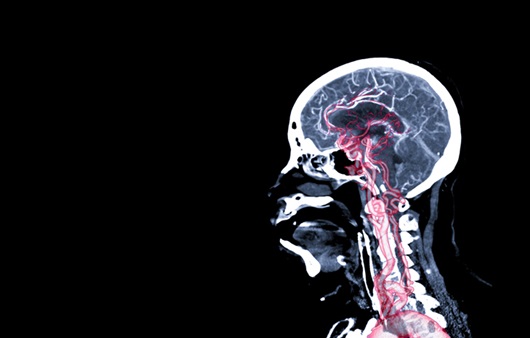

뇌 건강은 우리의 전반적인 건강과 일상생활에 중요한 영향을 미칩니다. 하지만 현대인의 생활 습관과 식습관으로 인해 뇌 건강이 위협받고 있는 상황입니다. 이러한 이유로 뇌혈관에 좋은 음식을 섭취하는 것이 더욱 중요해졌습니다.

이번 포스팅에서는 뇌혈관 건강을 지키는 데 도움이 되는 12가지 음식을 소개해 드리겠습니다. 이 음식들은 뇌 기능을 최적화하고 인지 능력을 높이는 데 기여할 수 있습니다.